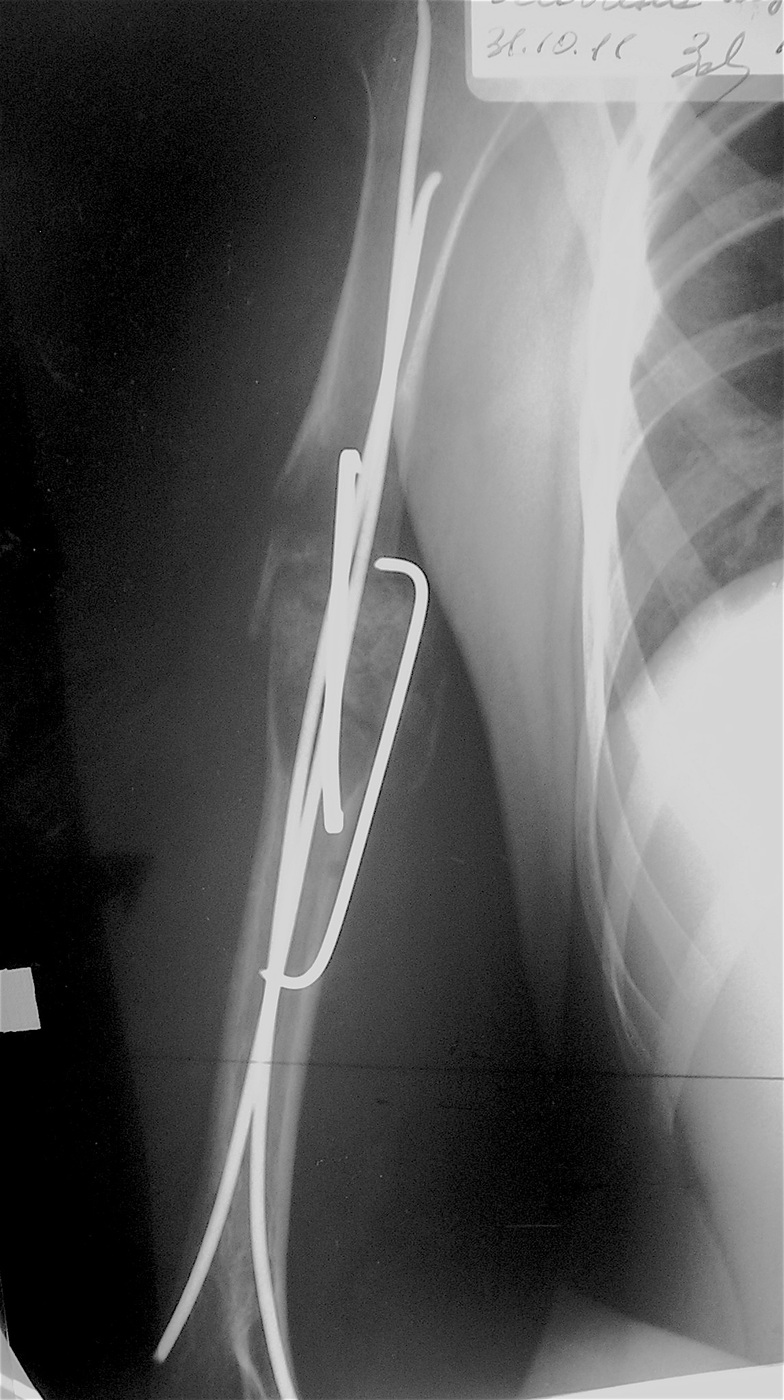

Закрытый, патологический перелом в с/з правой плечевой кости на фоне аневризмальной кисты диафиза правой плечевой кости.

Выполнена операция: экскохлеация кисты, остеосинтез титановыми эластичными стержнями и металлической скобой, аллопластика патологического очага материалом «Лиопласт».

Функция конечности сохранена, ребенок себя обслуживает.

Имеется укорочение правой верхней конечности  на 1,5 см за счет плеча.